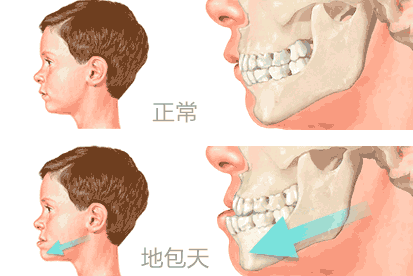

牙齿“地包天”是比较常见的牙齿发育畸形,是下颌前突前牙反颌的一种现象,它不仅影响面部美观,同时还影响牙周组织健康和口腔功能的正常发挥。海涛口腔牙齿矫正可以帮助您解决地包

天。但是在矫正前,一定要了解是什么原因造成的地包天,这样才能找到适合矫正地包天的方法。

2、骨源性:多由于遗传和疾病等因素所致,可表现为下颌角钝,下颌体长,下颌支短或上颌前部发育不足。

【温馨提示】:牙性地包天可以通过佩戴矫治器改变牙齿的咬合关系,而骨性地包天治疗较为复杂,需要在3-4岁时通过外科正牙手术才能纠正,如果勉强使用牙齿矫正,会出现反弹的现象。》》》怎么判断是牙性地包天还是骨性